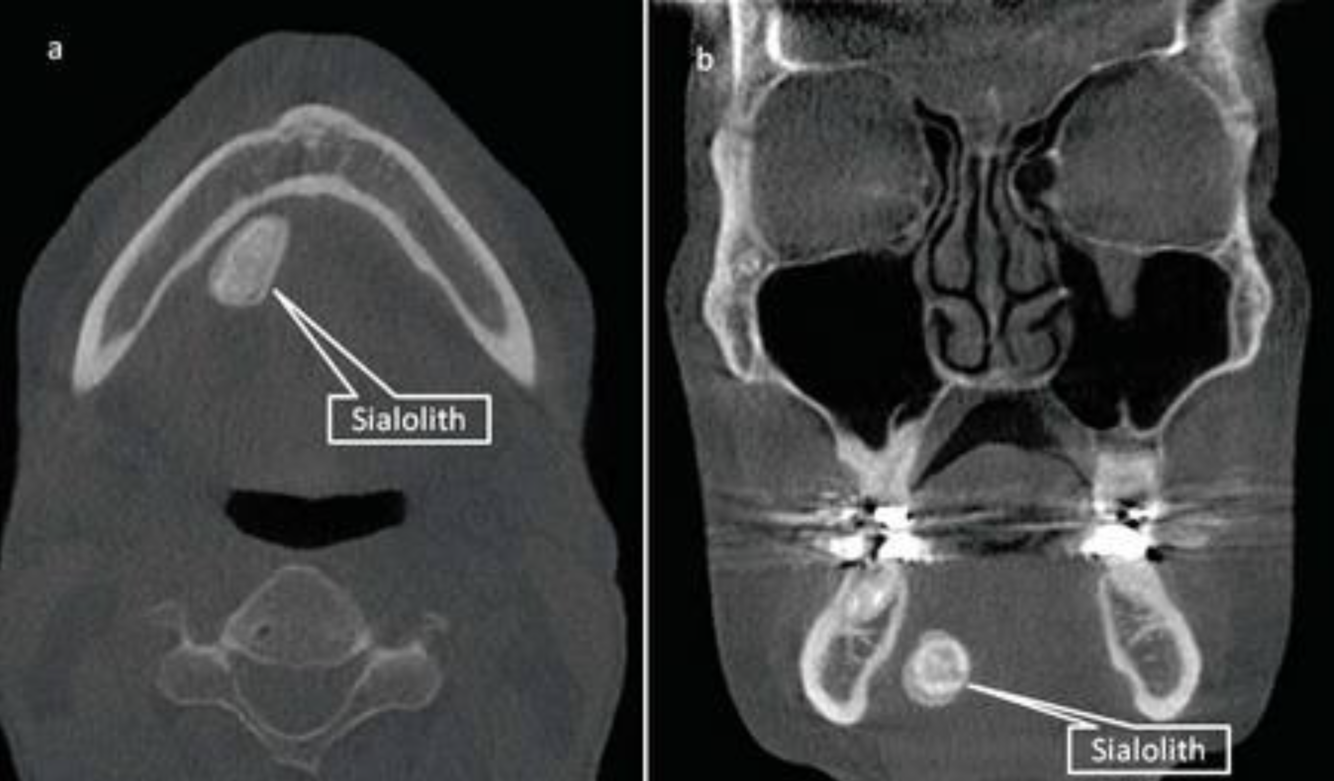

19

Q

What is a Sialolith

A

Submandibular gland stone